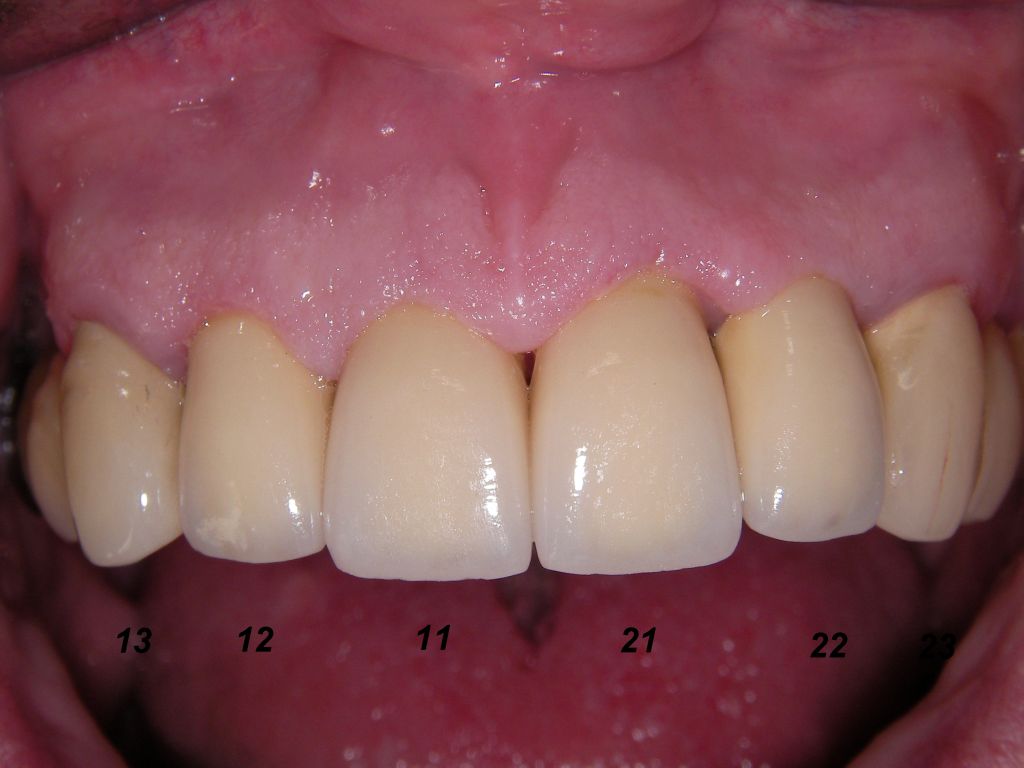

Weil auch die anderen Schneidezahnkronen (12-22) durch Randreparaturen und den schlechten Randschluß erneuerungsbedürftig aussahen, wurden 4 Einzelkronen geplant. Vorher hieß es aber noch, die schlechte Wurzelfüllung im Zahn 12 (Röntgenbild links) besser zu machen. Hierfür wurden am 17.2.06 die alten Kronen 11 und 12 entfernt. Rechts das Bild nach Entfernung von alten Füllungen und Karies. | |

Am 28.2.06 erfolgte die endgültige Präparation (das "Beschleifen") aller 4 Zähne. Links das Modell, auf dem die Kronen gefertigt worden waren. Rechts kurz vorm Zementieren der Kronen am 13.3.06. Aus der Längendifferenz der Zähne rechts und links kann man darauf schließen, daß die Präparation tief unter dem Zahnfleisch erfolgen mußte. |

Links die Kronen aus dem Dentallabor "Heitmeyer Zahntechnik", Osnabrück. Man sieht praktisch keinen Metallrand. Der Patient war zur Farbbestimmung im Dentallabor - so halten wir es praktisch immer. Rechts das Ergebnis bei der 1. Nachkontrolle am 27.3.05. Das Zahnfleisch muß sich noch etwas erholen. |